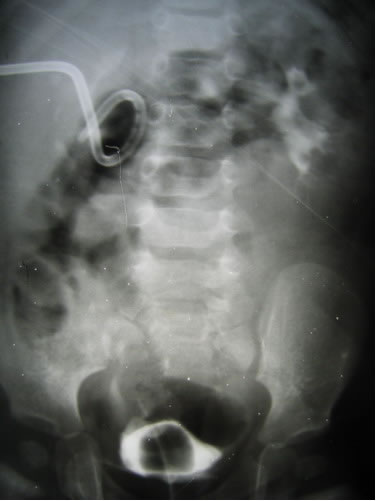

Мочевой пузырь дренирован катетером Фолей № 12F. Под ЭТН

произведен косой разрез в подвздошной области справа. Послойно

внебрюшинно выделен мочевой пузырь и суправезикальный отдел

правого мочеточника. Мобилизована нижняя треть правого мочеточника.

Последний расширен по всей длине, перистальтирует. Мочевой

пузырь прошит викрилом в зоне пузырно-мочеточникового сегмента

и мочеточник отсечен. Выполнено формирование 2-х подслизистых

тоннелей на мочевом пузыре по передне-боковой стенке длиной

2,5см., мочеточник проведен через тоннели и наложены уретероцистоанастомозы,

с предварительной интубацией мочеточника внутренними стентом

№ 6 F. Гемостаз. Послойное ушивание раны. Шов на кожу по

Холстеду. Обработка раны. Асептическая наклейка.

Оперировал А.Ю.Павлов.